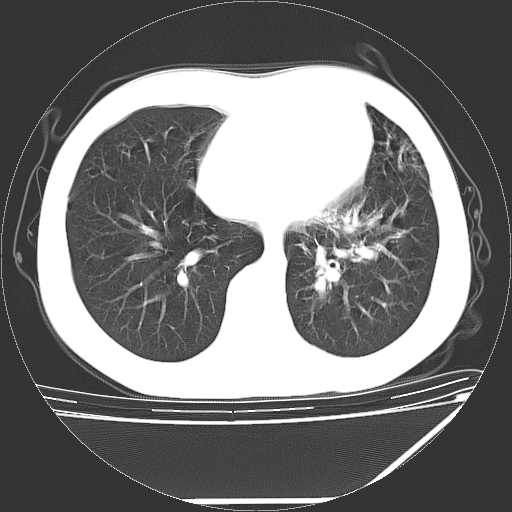

男,13岁,咳嗽、咳痰伴发热一周。

上纵隔课件多枚淋巴结,部分相互融合,左侧支气管壁增厚,肺纹理较右侧增粗,患者,男,13岁,

中上纵隔见多枚淋巴结肿大,部分相互融合成团片,左肺门增大,上叶支气管变窄,肺内多处斑片状 索条状及棉絮状致密影。临床“男,13岁,咳嗽、咳痰伴发热一周。”首先考虑:原发综合征!不除外淋巴瘤可能!

纵隔多发肿大淋巴结,部份有融合改变。双肺血管气管束增厚,以肺门为中心向外周散发,以左肺下叶为明显。考虑淋巴瘤可能性大。不除外原发综合征。

中上纵隔见多枚淋巴结肿大,部分相互融合成团片,左肺门增大,上叶支气管变窄,左肺支气管血管束增粗,可见磨玻璃样影。临床“男,13岁,咳嗽、咳痰伴发热一周。”首先考虑:淋巴瘤可能性大!

左肺野见淡片状影,病因整体多考虑结核